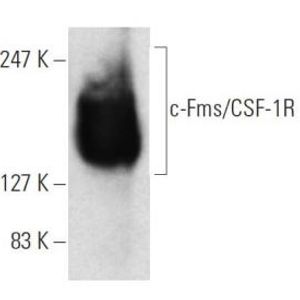

JUL 28, 2025Drug Discovery & DevelopmentOne lab technique that has been around since what feels like the dawn of time is Western blotting, and it doesn&r ...